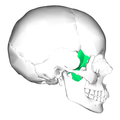

| Partie orange | Incus | 16%

| Partie marron | Stapes | 14%

| Partie beige | Malleus | 7%